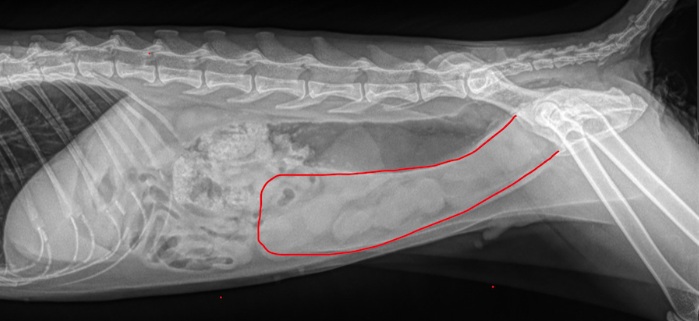

- Ultrasound or X-rays are done to deeply inspection of the fluids and other liquids in the abdomen.

Imaging is especially important to confirm whether the uterus is enlarged and infected.